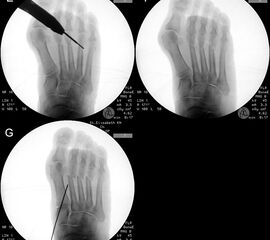

Zum Lesen der Bildbeschreibung und zur Vollansicht bitte das Bild anklicken.

Zum Lesen der Bildbeschreibung und zur Vollansicht bitte die Bilder anklicken.